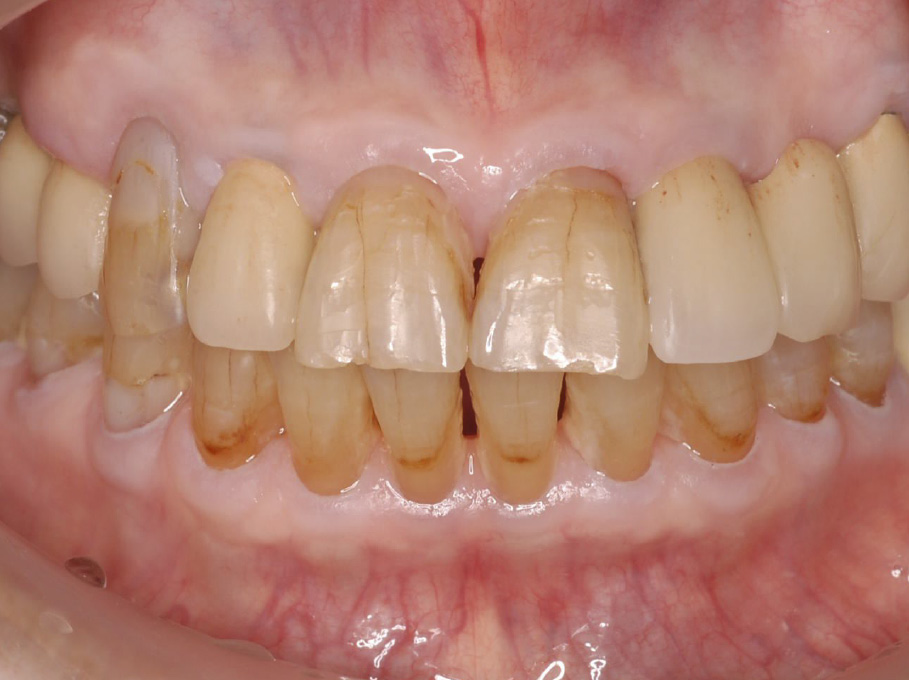

現 症: 1) 口腔内所見全顎的に歯肉の発赤・腫脹を認め,O'Learyのプラークコントロールレコード(PCR)は100%であった。また,多量の厚いプラークが付着しており,下顎前歯部舌側には歯冠を覆うように歯肉縁上歯石の付着を認めた。歯冠破折部位も認められ,多部位にう蝕を確認した(図1)。

初診時の口腔内写真(2004年7月)

全顎的に多量の歯石沈着,歯肉に発赤・腫脹を認めた。